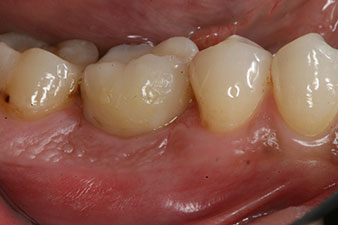

Les dernières photos montrent la couronne composite monolithique retenue par une vis une fois mise en place et la radio de contrôle (Fig. 9 et 10) (6).

couronne composite

Fig. 9 : La couronne composite définitive est scellée sur un pilier hybride PEEK en laboratoire et peut être vissée en place immédiatement.

radio de contrôle

Fig. 10 : La radio de contrôle montre que l’ostéo-intégration a été réussie et que la couronne est vissée en position de manière parfaitement ajustée.